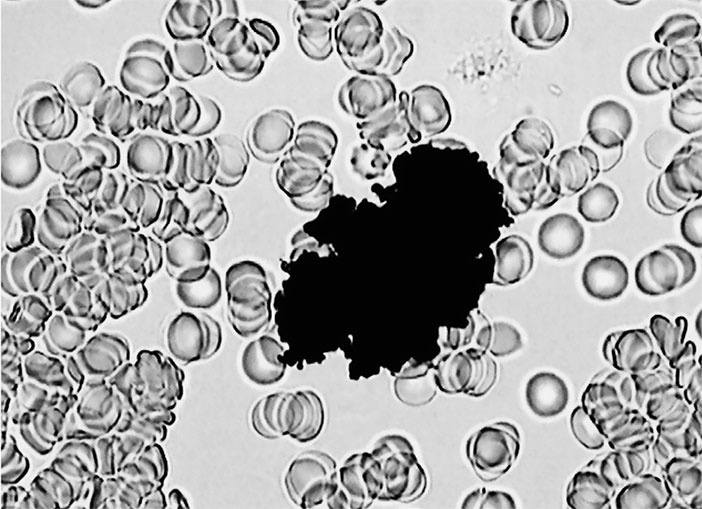

Давайте посмотрим на «неопознанного паразита» при большом увеличении и сравним с личинкой паразита, которую мы уже видели. ![]() Антенна-4 Что бросается в глаза? Личинка – гладкая, гибкая, без каких-либо выступов и узлов, приспособленная для передвижения в стесненных условиях. А «неопознанный паразит» весь покрыт длинными выростами, которые наверняка будут затруднять его продвижение. Кроме того, у личинки можно без труда определить, где вход в кишечный тракт (рот), а где из него выход (не рот). У волосатого чудища ни первое, ни второе найти не получается. Да и размеры просто гигантские: такое не то что в капилляры – не в каждую вену поместится. Итак, как и в примере с личинкой паразита, мы имеем дело со срежиссированным артефактом. Нечто таких размеров и очертаний через прокол в подушечке пальца не сможет выбраться ни при каких условиях, то есть наблюдаемое в микропрепарате привнесено извне. И в данном случае можно точно установить, что это и откуда оно взялось. Помните, мы говорили о том, что гемосканирование обычно проходит в не приспособленных для этого помещениях, грязных с точки зрения требований к клинической лаборатории? Так вот, «неопознанный паразит» попал в каплю крови из воздуха, и на самом деле это обломок хитиновой антенны комара-звонца. На фотографии с сайта Университета Мичигана очень хорошо видно сходство. ![]() Комар-звонец Кристаллы В нашем организме действительно могут образовываться кристаллы. Чаще всего в моче, но и в крови они иногда встречаются. Например, игольчатые кристаллы уратов (солей мочевой кислоты) при подагре. Их можно увидеть после определенной подготовки (фиксация, окраска) [62] препарата крови, однако при гемосканировании их почему-то обнаруживают и в живой капле, причем в очень интересном виде. ![]() Мочевая кислота Ну да, некая игольчатость присутствует, края острые, похожие на осколки… Постойте, но ведь это и есть осколки! Присмотритесь, отлично видно, что стекло треснуло в центре от давления сверху. Так происходит, когда неопытные лаборанты или студенты слишком быстро выкручивают винт, приближающий объектив микроскопа к предметному столику. Линза сначала упирается в лежащее сверху препарата тонкое покровное стекло, а затем раздавливает его с характерным грустным хрустом. Кроме того, попадаются особенно сильные уникумы, умудряющиеся сломать таким манером и куда более толстое предметное стекло, на которое наносится капля крови или образец другой ткани. Впрочем, в атласе встречаются и более экзотические примеры. Вот, скажем, кристаллы ортофосфорной кислоты. ![]() Ортофосфорная кислота Этим микропрепаратом рекомендуется пугать подростков, любящих пепси или кока-колу. Не знаю, как такое зрелище действует на неокрепшие детские умы, но у человека, имеющего большой опыт работы с микроскопом и обладающего познаниями в клинической лабораторной диагностике, оно вызывает лишь смех. Во-первых, ортофосфорная кислота прекрасно растворяется в воде [63], и с 1952 года, которым датирован указанный в сноске справочник, ровным счетом ничего не изменилось. Во-вторых, кристаллизуются ее полугидраты, и итоговые кристаллы получаются белого цвета, а не черного. В-третьих, для кристаллизации при температуре тела требуется настолько высокая насыщенность раствора [64], что это должна быть кровь Чужого, а не человека. В-четвертых, если присмотреться, можно заметить, что черное пятно находится на переднем плане, то есть не внутри крови, а как бы перед ней. И это ощущение абсолютно правильное. С подобными «кляксами» сталкивались многие лаборанты: это самая обычная грязь на линзе объектива. С «кристаллами сахара», которые, по мнению составителей атласа, запечатлены на следующей фотографии, история примерно та же. ![]() Кристаллы сахара Во-первых, «сахара» в крови нет. Основной простой углевод нашего организма – моносахарид глюкоза. И авторам якобы медицинского издания неплохо бы это знать. Во-вторых, глюкоза в той концентрации, в которой она присутствует в крови, и при температуре тела кристаллизоваться не может [65], ей запрещают это делать законы химии и физики. Вспомните, когда засахаривается мед или варенье. Приблизительно столько же «сахара» должно быть и в крови. Холестерин Вообще-то в соответствии с химической номенклатурой этот жирный спирт положено называть холестеролом, но, чтобы вы, уважаемые читатели, окончательно не запутались, воспользуемся устоявшимся в русском языке, хотя и некорректным термином. Вот так, по мнению авторов атласа, выглядит под микроскопом холестерин. ![]() Холестерин |